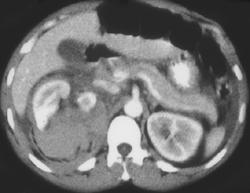

Lymphoma With Perirenal Spread of Tumor in Left Perirenal and Pararenal Space